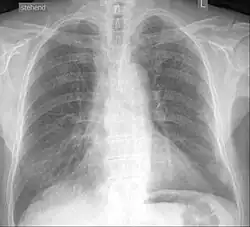

Die Wechselwirkungen partikulärer Fremdkörper mit dem Organismus lassen sich in vielen Fällen nicht vorhersagen und werden daher häufig im Tiermodell untersucht. So sind beispielsweise Titanweiß oder auch Ruß beziehungsweise Kohlenstaub unlöslich und chemisch inert und führen weder zu Entzündungsreaktionen noch zu Schädigungen der Makrophagen beziehungsweise des Lysosoms. Die exogenen Partikel werden in den Histozyten eingelagert.[1] Im Fall der Kohlenstoffpartikel werden diese Zellen schwarz pigmentiert (anthrakotisches Pigment). Das Lungengewebe von Bergleuten, die Kohlenstaub ausgesetzt sind, ist häufig tiefschwarz pigmentiert. Diese Ablagerungen führen – sofern es sich nur um Kohlenstaub handelt – nicht zu pathologischen Veränderungen der Zellen oder des umgebenden Gewebes.[3] Auch kristallines Siliciumdioxid und Bariumsulfat sind unlöslich und chemisch inert. Inhalierte Stäube kristallinen Siliciumdioxids (Quarz) können aber zu der bei Bergleuten gefürchteten Silikose, einer Fremdkörperreaktion, führen.[4] Bariumsulfat ist ein seit vielen Jahrzehnten bewährtes und bei oraler Gabe ungefährliches Röntgenkontrastmittel. Wird es versehentlich intraperitoneal (in die Bauchhöhle) appliziert, so ist dieser Irrtum in 20 bis 50 Prozent der Fälle letal.[5][6]